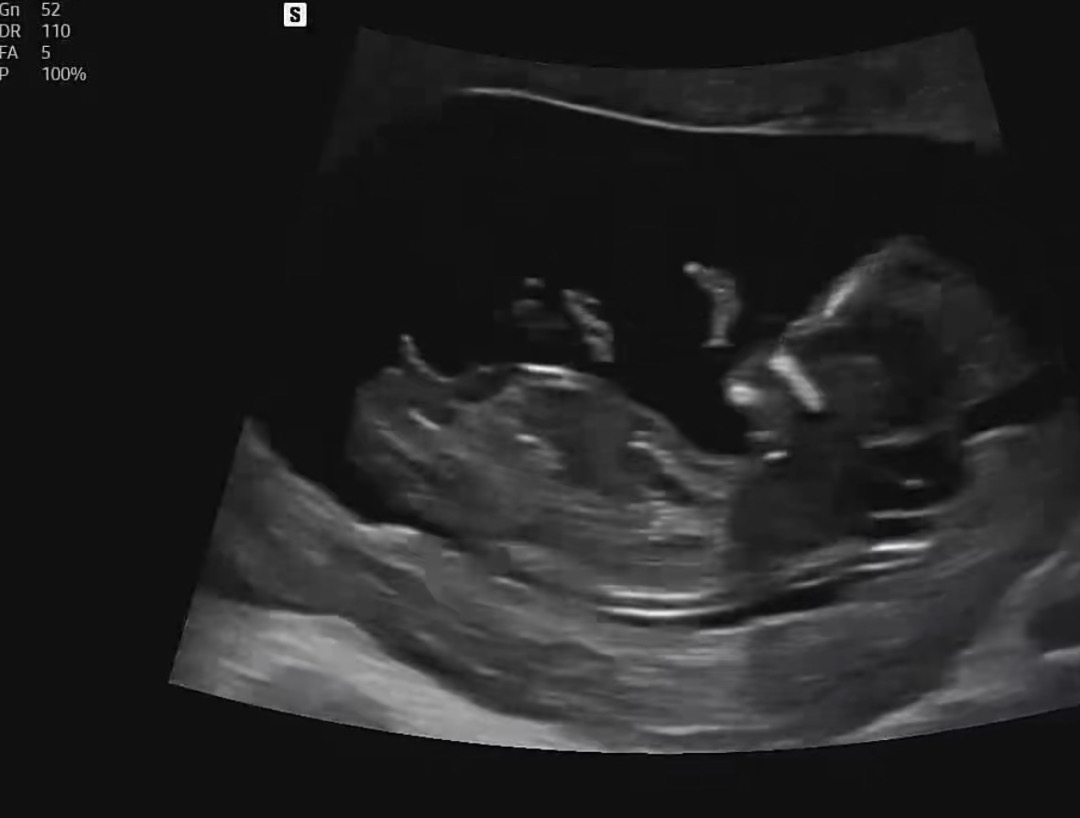

12주 각도법 한번 봐주세요 🥹

딸 아들 어떻게 보이시나요ㅎㅎ🤣💕

우아 완전 아들각도네여!